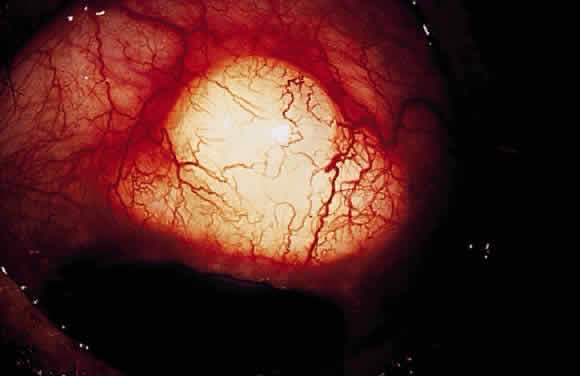

Some patients with intraocular hypotony develop loss of central vision secondary to marked irregular folding of the choroid and retina. Initially, these folds are broad and not sharply delineated. They tend to radiate outward in a branching fashion temporally from the optic disc and concentrically or irregularly nasally to the disc. There may be swelling of the peripapillary choroid simulating papilledema (Fig. 3). The retina often shows a series of stellate folds around the center of the fovea. The retinal vessels are tortuous and sometimes engorged. The primary cause of visual loss is the marked folding of the central retina. Early detection of this condition is important because correction of the cause usually results in visual improvement. In cases of prolonged hypotony, permanent pigmented lines, caused by changes in the retinal pigment epithelium, occur in the macular area and nasally. A postoperative bleb leak and a cyclodialysis cleft were formerly the most common causes of hypotony maculopathy. The incidence of hypotony maculopathy after glaucoma surgery has increased with the use of antifibrotic agents, specifically mitomycin C. A direct toxic of mitomycin cannot be ruled out. The maculopathy is most likely to occur in young myopic patients, who may have a sclera more susceptible to swelling and contraction.11–14

Fig. 3. Fundus photograph. Hypotony maculopathy with choroidal folds, retinal striae, and marked swelling of the peripapillary choroid simulating papilledema.